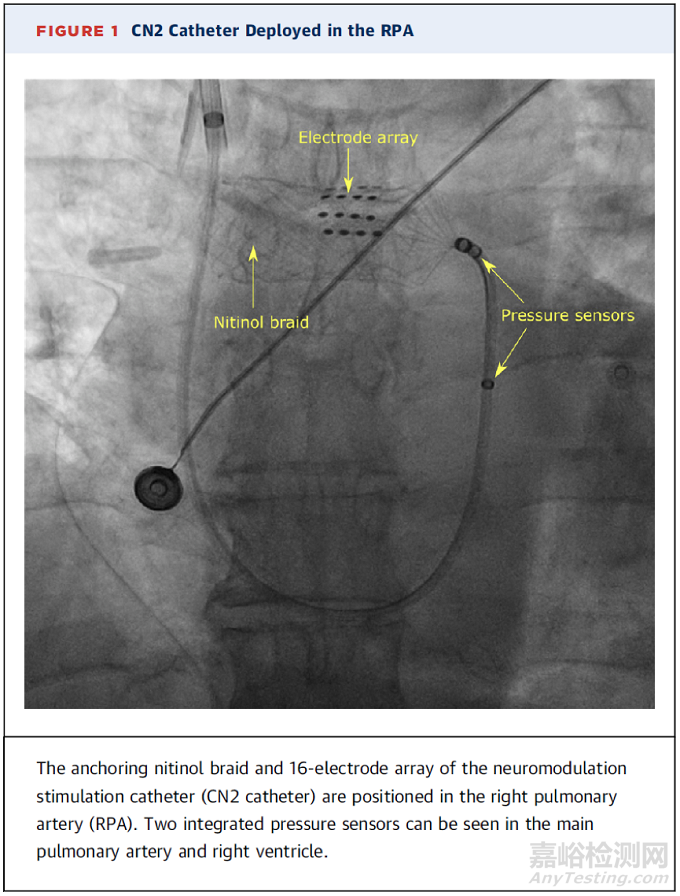

心肺神經(jīng)刺激(CPNSTM)系統(tǒng)(Cardionomic,Inc)是一種基于導(dǎo)管的研究設(shè)備,旨在電刺激右肺動(dòng)脈(RPA)周圍的心臟自主神經(jīng)。CPNS系統(tǒng)使用臨時(shí)經(jīng)皮裝置可改善心臟功能,增加全身灌注。

CN2導(dǎo)管使用標(biāo)準(zhǔn)的右心導(dǎo)管介入技術(shù)和透視引導(dǎo)通過頸內(nèi)靜脈經(jīng)皮輸送到RPA內(nèi)的目標(biāo)治療位置。定位后,CN2導(dǎo)管就會(huì)被部署在血管壁上提供相應(yīng)刺激?;谟^察到的生理反應(yīng)調(diào)整電流強(qiáng)度。一旦達(dá)到理想的反應(yīng),該系統(tǒng)可以保持原位并提供長(zhǎng)達(dá)5天的治療。最初的單中心、首次人體概念驗(yàn)證研究發(fā)現(xiàn),患者左室內(nèi)壓變化速率和平均動(dòng)脈壓分別增加了22.6%±4.8%(P=0.006)和13.5%±3.8%(P=0.006)。沒有報(bào)告嚴(yán)重的不良事件,也沒有觀察到心率的顯著變化。這項(xiàng)研究表明,在心力衰竭患者的心率沒有顯著變化的情況下,該設(shè)備可以增加左室收縮力和動(dòng)脈血壓[15]。隨后的新型CPNS2系統(tǒng)研究也同樣顯示CPNS系統(tǒng)可以在保持安全性的同時(shí)增加左室收縮力,對(duì)心率產(chǎn)生中性影響。